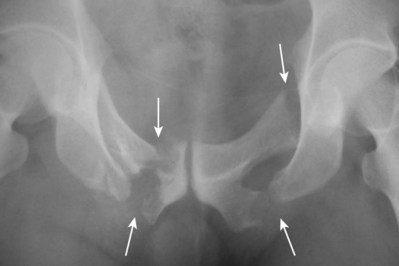

Urethral disruption injuries typically occur in conjunction with multisystem trauma from vehicular accidents, falls, or industrial accidents. Fracture of the anterior pelvic ring or pubic diastasis are almost always present when urethral disruption is encountered, and a greater degree of displacement has been correlated to a higher risk of urethral injury (Basta et al, 2007). “Straddle fractures” (Fig. 88–13 on the Expert Consult website)

involving all four pubic rami and fractures resulting in both vertical and rotational pelvic instability are associated with the highest risk of urologic injury (Mundy, 1996; Koraitim, 1999; Brandes and Borelli, 2001). Urethral injury has been reported to occur in approximately 10% of males and up to 6% of females sustaining pelvic fractures (Koraitim et al, 1999; Black et al, 2006). Girls younger than age 17 years have a higher risk of urethral injury compared with women, perhaps owing to greater compressibility of the pelvic bones (Hemal, 1999).

Figure 88–13 Anteroposterior film of the pubis shows a straddle fracture involving all four pubic rami (arrows) in a patient with a posterior urethral disruption in whom initial perineal posterior urethroplasty failed because of severe bone distortion. Reconstruction was successfully performed by an abdominoperineal technique.